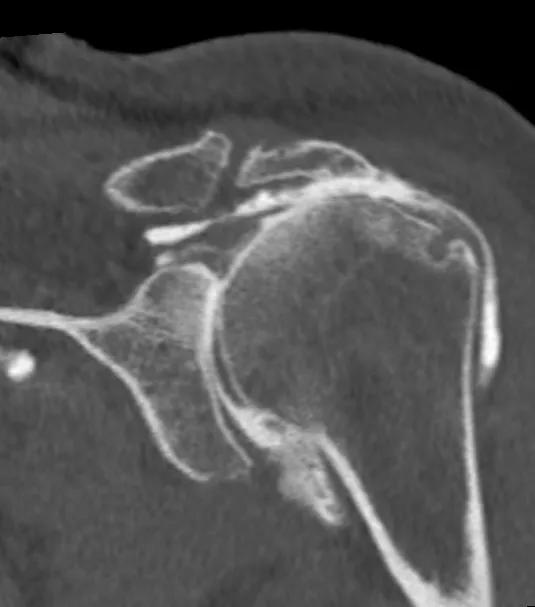

Arthroscanner d'une omarthrose secondaire secondaire à une lésion de la coiffe des rotateurs.